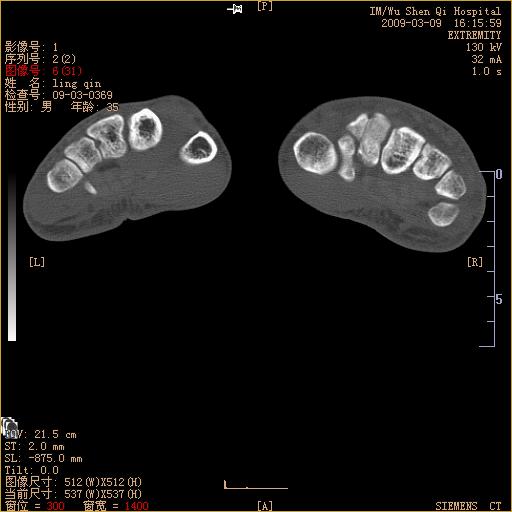

请上传x线平片。舟状骨骨折可能大。

舟状骨骨折。

左侧舟骨及桡骨茎突骨折,第一掌骨基底部好像也有骨折,建议上传平片